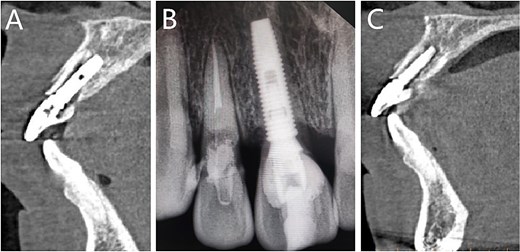

The patient fell down the stairs and injured his maxillary anterior teeth one day before (Fig. 1).

(A) The whole teeth photograph; (B) The fracture lines in teeth 11 and 12.

Midline smile line; gingivitis with bleeding on probing; absence of occlusal interference. Severe percussion pain (+++) was observed in teeth 11 and 12. Teeth 11 and 12 exhibited crown fracture with grade-III mobility of the fractured segment.